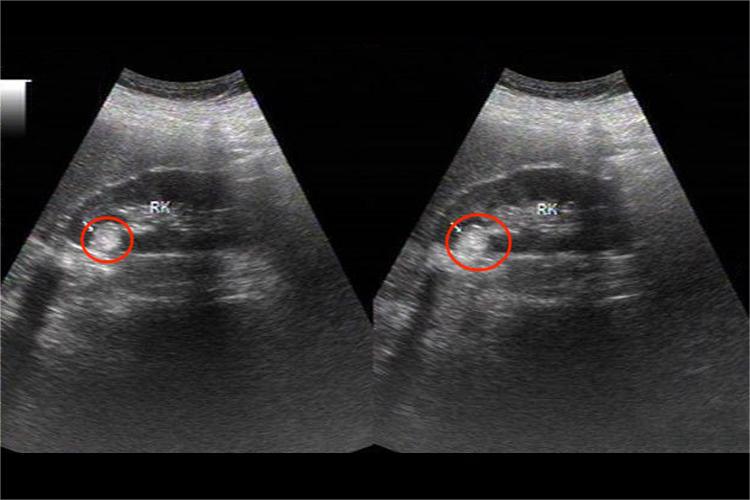

肾错构瘤的超声表现在声像图上,肾错构瘤与正常肾组织有明显界限,但无包膜。声像图表现可分为两种类型。

一种为边界清晰的圆形强回声,后方多无衰减或衰减不明显,常位于肾的表面或接近肾的表面,在肾上极者尤为常见。

另一种内部回声强弱交错,典型的呈洋葱片样图形,强弱回声层层间隔,有序排列。